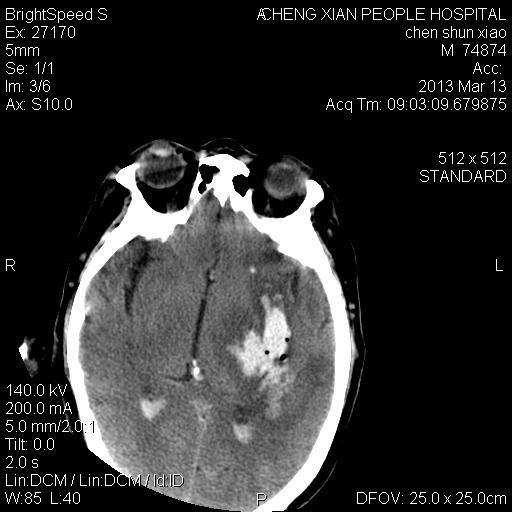

患者陈++,男,71岁。因“昏迷四小时,伴右侧肢体活动受限”以“脑出血”收住院。发病后12小时用“改良立体定向-软通道微创介入新技术治疗脑出血”。术后24小时颅内出血大部被清除,患者神志清晰。右侧肢体肌力0级。

患者陈++,男,71岁。因“昏迷四小时,伴右侧肢体活动受限”以“脑出血”收住院。发病后12小时用“改良立体定向-软通道微创介入新技术治疗脑出血”。术后24小时颅内出血大部被清除,患者神志清晰。右侧肢体肌力0级。